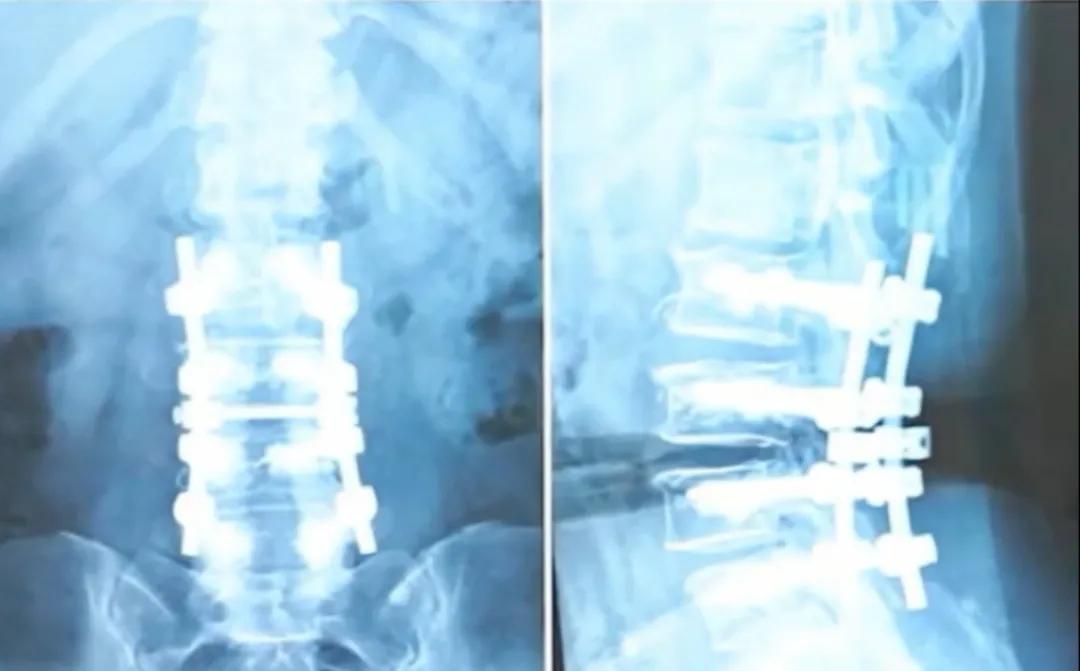

Take, for example, the patient in her 50s featured in the video. She underwent surgery due to severe spinal stenosis and osteoporosis. To maintain spinal stability, Dr. Wang implanted 4 pairs (8 total) of screws in her lumbar spine and performed vertebral body augmentation using bone cement. While such a procedure may sound extensive, surprisingly, her lumbar flexibility remained excellent post-surgery, even allowing her to touch the ground with both hands.